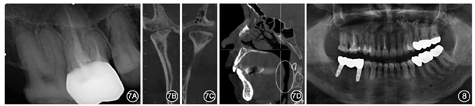

架,检验修复体并适当染色后戴入患者口内(图6)。此时已完成12、16根管治疗及45—47种植体支持的固定桥修复(图7A)。戴牙后即刻,1周,1、3个月复查,患者对疗效满意,无明显不适,实现最初的设计要求。戴牙后6个月数字化

力分析仪(T-scan Ⅲ,Texscan,美国)测试结果显示,

力中心点位置趋于中央,位于磨牙和前磨牙区。右侧后牙区因有种植体支持的固定桥,咬合设计为轻咬时种植修复体与对

牙不接触,重咬时种植修复体与对

牙轻接触。锥形束CT示双侧髁突位置居中,基本对称,左侧髁突骨皮质变得光滑连续,有骨改建表现,与治疗前相比有明显改变(图7B,图7C);治疗后患者自述打鼾情况减轻,睡眠质量提高,回顾治疗前后气道宽度发现治疗后气道变宽(图7D)。随访1个月患者曲面体层X线片示修复体边缘密合,45、47种植体骨结合良好,未见明显骨吸收(图8)。